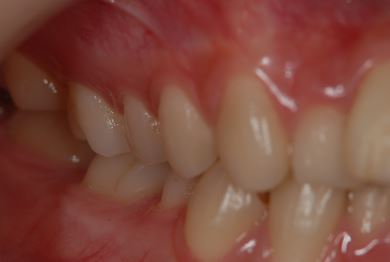

セラミック治療

| 性別/年齢 | 女性 / 20歳 | ||||||||||||||||||||||||||||||||

| 主訴 | 神経が死んで来ている歯が痛むので、治療をして欲しい。歯並びも良くできるのであればして欲しい。 | ||||||||||||||||||||||||||||||||

| 治療方針 | ジルコニアオールセラミック(クラウン1本、ブリッジ3本)、セラミック用土台2本 | ||||||||||||||||||||||||||||||||